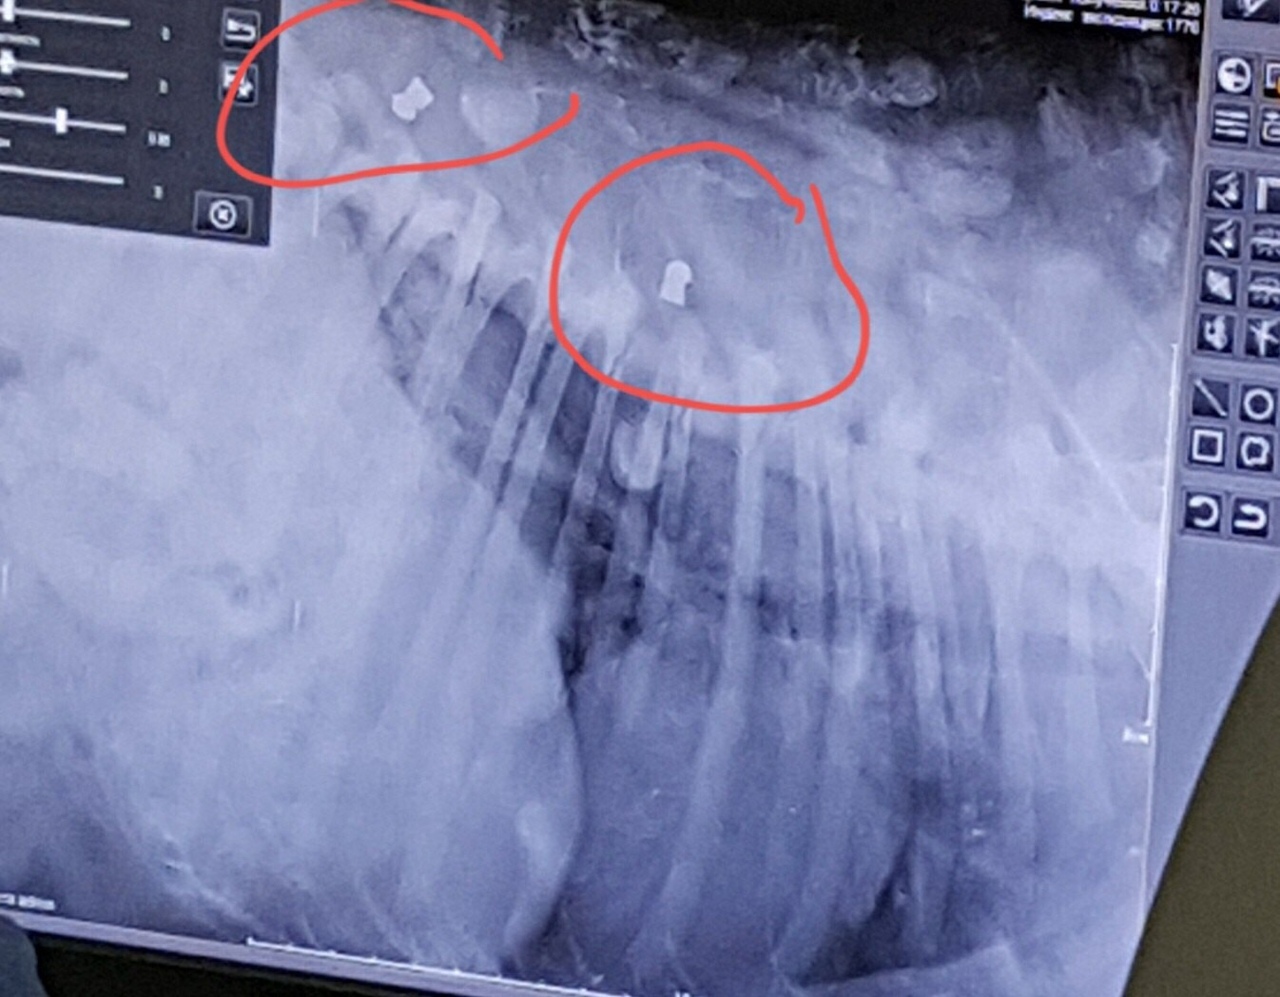

(Рентгеновский снимок одной из пострадавших собак, фото из соцсети ВКонтакте)